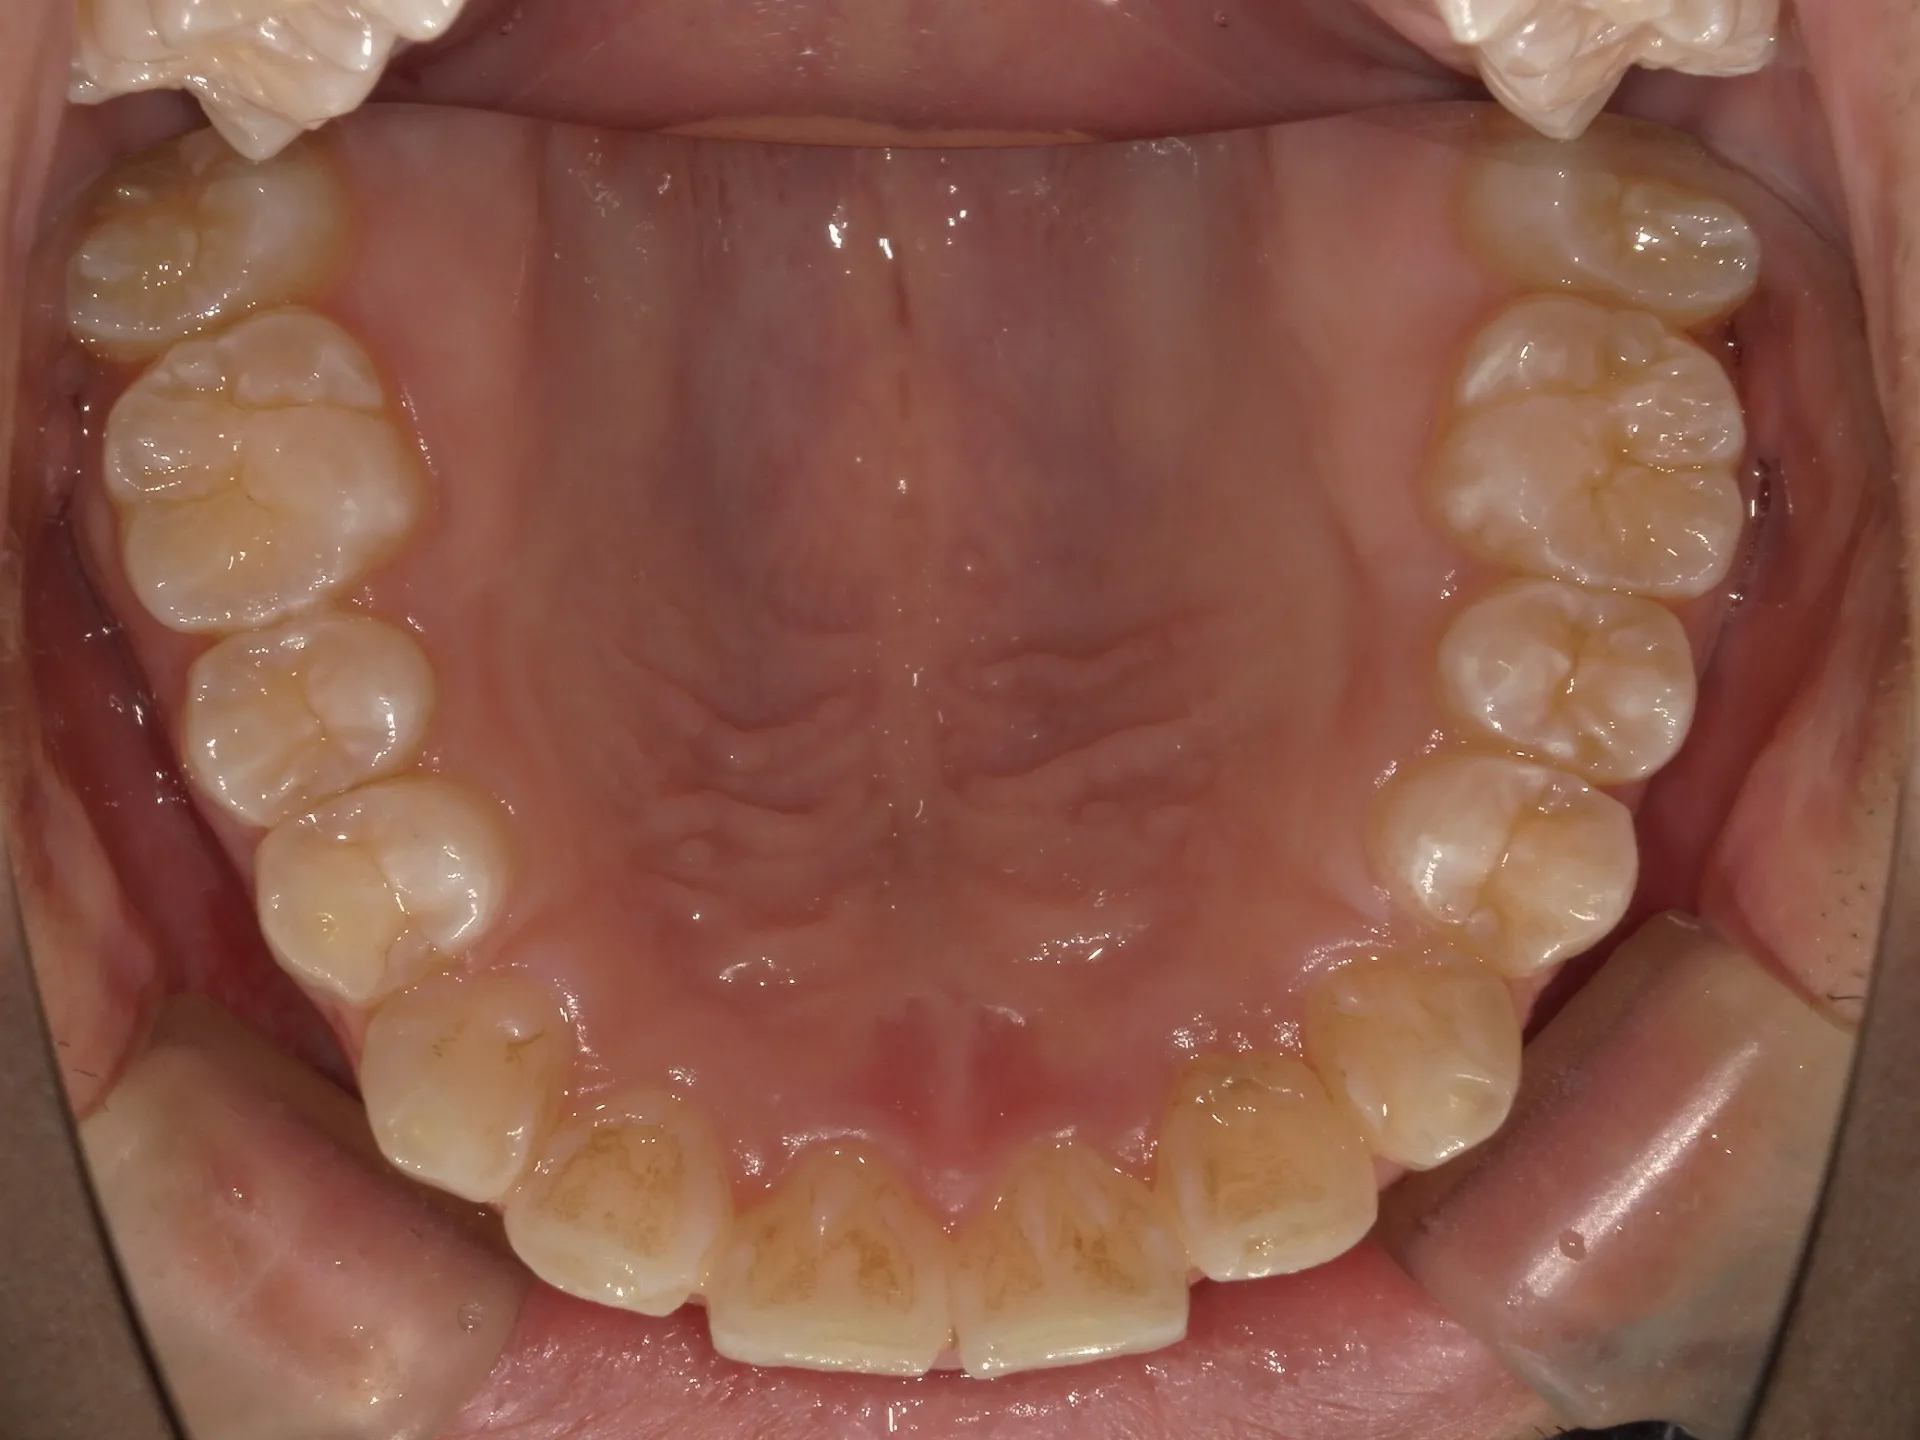

今回は他院さんでインビザライン矯正治療を受けていた患者様を引き継いで当院でインビザライン治療を継続した症例をご紹介致します。

今回はマウスピース矯正を主軸にした矯正ですが、一部ワイヤー矯正も併用して改善しております。